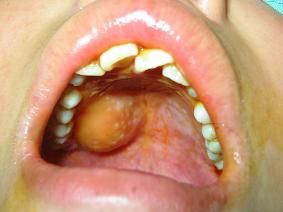

頜面部腫瘤頜面部有骨組織和軟組織,頜面部的器官包括口腔、唾液腺、顳下頜關節。頜面部腫瘤常見以下幾種:①牙源性腫瘤。牙齒髮育過程中形成的頜骨腫瘤。良性的有造釉細胞瘤、牙源性腺樣瘤、牙源性鈣化上皮瘤、牙源性鈣化囊腫、真性牙骨質瘤、牙源性纖維瘤、牙源性粘液瘤、複合牙瘤、組合牙瘤等。惡性的有造釉細胞癌、造釉細胞纖維肉瘤等。②一般組織來源腫瘤。良性的有乳頭狀瘤、唾液腺混合瘤、纖維瘤、脂肪瘤、粘液瘤、軟骨瘤、骨瘤、纖維骨瘤、血管瘤、淋巴管瘤、神經纖維瘤、神經鞘瘤等;惡性的有鱗狀細胞癌、基底細胞癌、腺癌、腺樣囊性癌、乳頭狀囊腺癌、粘液表皮樣癌、纖維肉瘤、骨肉瘤、惡性淋巴瘤、黑色素瘤、神經纖維肉瘤、橫紋肌肉瘤等。以手術、化療、放射治療、免疫療法及中草藥等綜合治療為主。③頜面部囊腫。牙源性囊腫有牙根端囊腫、含牙囊腫、角化囊腫等;發育異常囊腫有正中囊腫、鼻齶囊腫、球狀上頜囊腫、鼻唇囊腫、甲狀舌囊腫、皮樣囊腫、腮裂囊腫;瀦留囊腫有舌下腺囊腫和粘液腺囊腫。頜骨囊腫表現慢性頜骨膨隆,骨皮質變薄和吸收變軟,呈囊性感,無痛,可繼發感染,X線照片可見頜骨膨隆,有透亮區,其邊界圓滑,有白線及牙齒的改變。以手術摘除囊腫為主,也要治療病源。